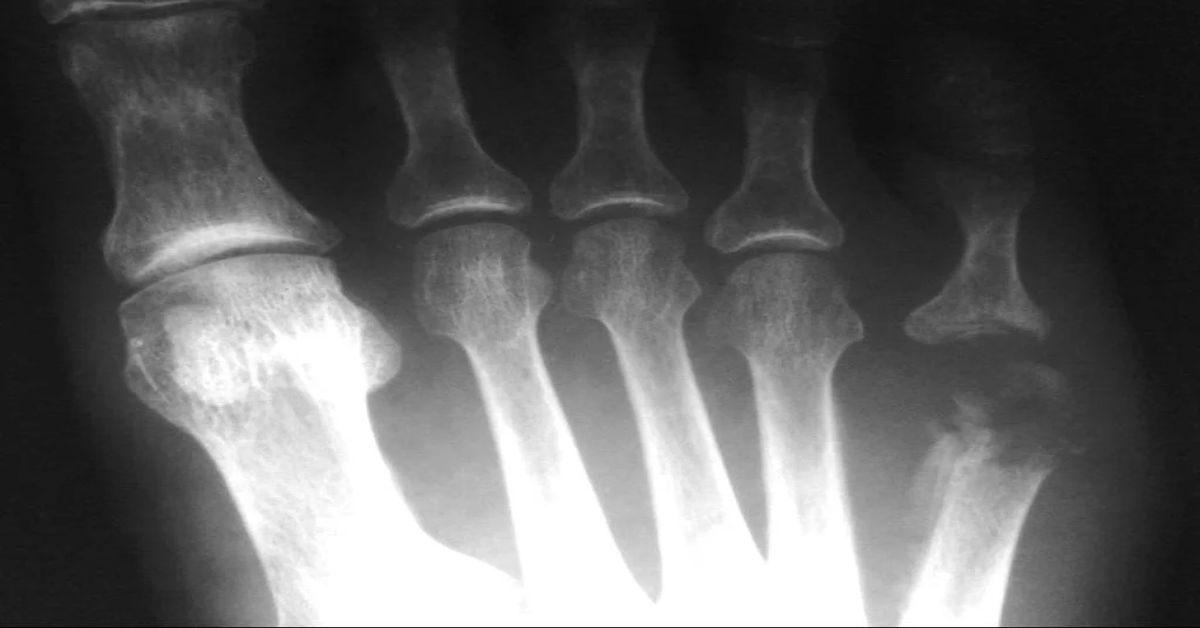

Şeker hastalığı olan kişilerde özellikle ayak yaraları geç iyileşir. Bu yaralardan vücuda giren bakteriler kemik dokusuna kadar ilerleyebilir. Aynı şekilde, damar tıkanıklığı gibi dolaşımı bozan hastalıklar da kemiğe yeterli oksijen ve bağışıklık hücresi ulaşmasını engelleyerek enfeksiyon riskini artırır.